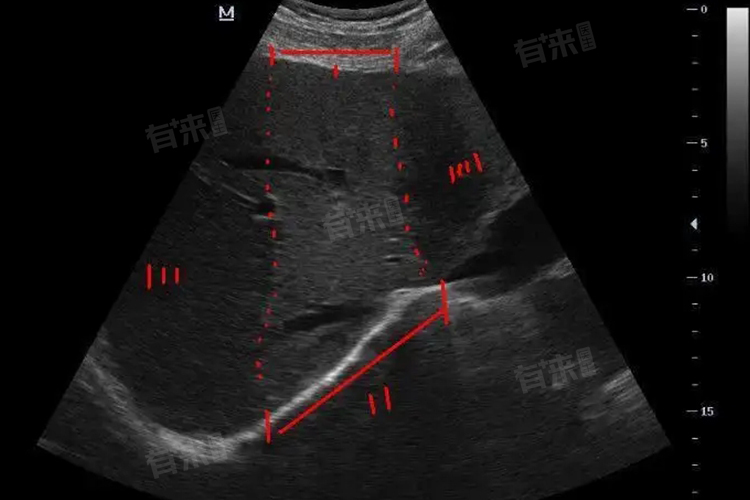

- 影像学检查:如超声、CT、MRI等,可以观察占位性病变的形态、大小、位置以及与周围组织的关系,为诊断提供重要依据。